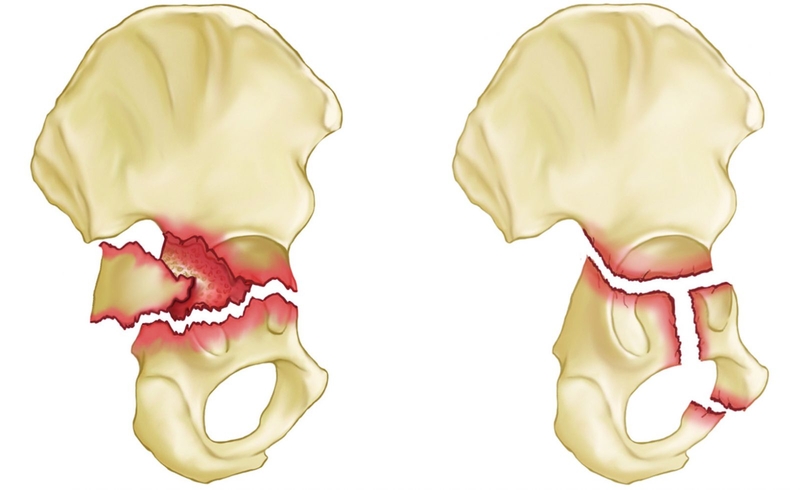

Gãy xương chậu hông có thể chia thành hai trường hợp: Gãy từng phần xương chậu và gãy khung chậu. Gãy khung chậu chiếm tỷ lệ tương đối thấp, chỉ từ 1 - 3% tổng số các trường hợp gãy xương. Tuy nhiên đây lại là những tổn thương nặng nề, phức tạp và có tỷ lệ tử vong cao thứ hai chỉ sau nguyên nhân chấn thương sọ não. Điều trị gãy khung chậu bao gồm điều trị bảo tồn, điều trị kết xương bên trong, điều trị bằng khung cố định ngoài,...

Tình trạng gãy ổ cối

Gãy xương vùng chậu còn có thể được phân loại theo kiểu gãy xương “ổn định” (stable) hoặc “không ổn định” (unstable). Dựa vào mức độ toàn vẹn của cấu trúc vùng chậu sau khi xảy ra chấn thương.